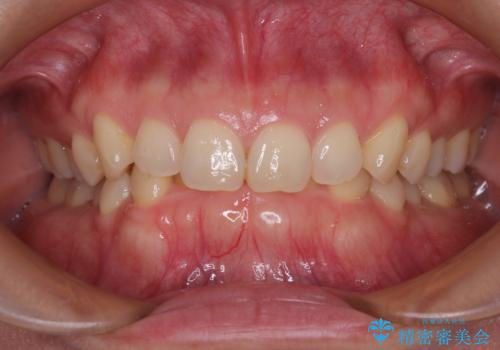

- 下顎前歯が完全に隠れてしまっていることを気にして来院された患者様です。

下顎の臼歯が手前に傾斜していることで咬み合わせが深くなってしまい、下顎前歯が見えないほどに上顎前歯が覆い被さっている状態でした。